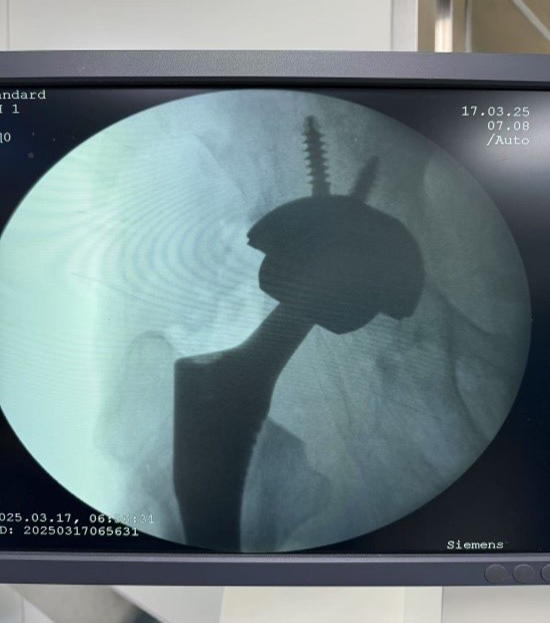

患者吕先生因高空坠落导致股骨颈骨折,进行股骨颈空心钉内固定术治疗,2年后,病情转为创伤性股骨头坏死,股骨头塌陷、变形,患肢短缩,疼痛难忍,行走困难,严重影响日常生活。传统髋关节置换手术依赖医生经验,假体植入角度和位置可能存在偏差,影响术后关节功能及远期假体使用寿命。此次手术中,陈柯主任团队利用国产“骨圣元化”关节手术机器人,通过术前精确的骨骼CT扫描,生成患者髋关节三维模型,工程师团队通过机器人系统自动规划出最佳假体型号、植入角度及深度,为吕先生量身定制了手术方案。术中,手术团队密切配合,机械臂在导航引导下精准打磨髋臼、安装假体,误差控制在0.5毫米以内,确保假体与患者骨骼完美匹配。手术过程顺利,术后病人恢复良好。